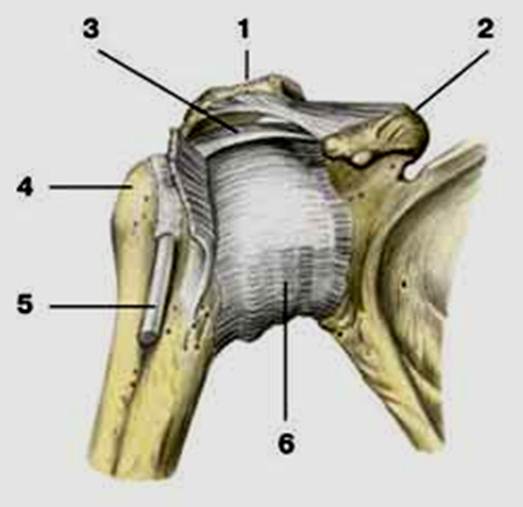

S: Цифра 1 обозначает головка плечевой кости.

S: Цифра 5 указывает на хирургическая шейка плечевой кости.

S: Стрелка указывает на большой бугорок плечевой кости.

S: Стрелка указывает на малый бугорок плечевой кости.

S: Стрелка указывает на art. humeri (латинский язык).

S: Стрелка указывает на lig. coracoclaviculare

Стрелка указывает на lig. Acromiclavicularis

S: Стрелка указывает на tendo m bicipitis brachii

S: Стрелка указывает на lig. coracoacromiale

S: Цифрой 6 обозначена суставная капсула плечевого сустава (русский язык).